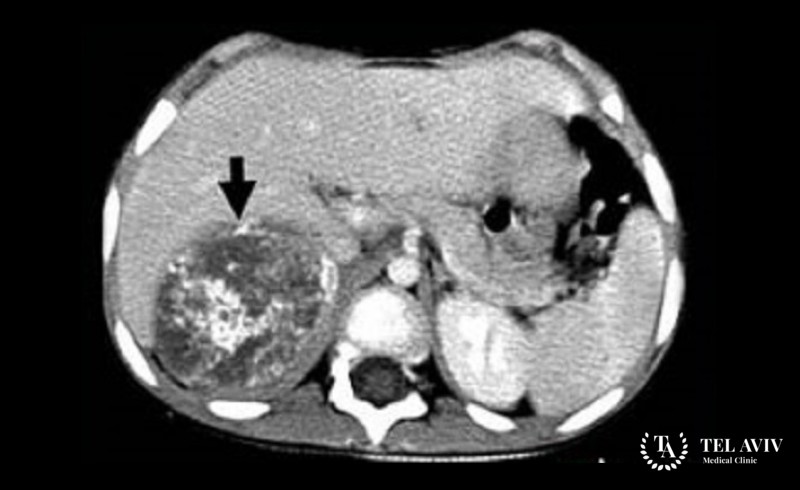

Нейробластома надпочечника – злокачественное образование, которое развивается в надпочечнике. Специалисты считают, что патология является наследственной и отличается своим агрессивным развитием. Опухоль быстро растет, проникает во внутренние структуры и дает метастазы по всему телу. Зачастую врач может обнаружить заболевание у молодых людей до 30 лет. К сожалению, на ранней стадии патологию обнаружить проблематично, так как симптоматика выражена слабо. Опухоль вызывает чрезмерную выработку катехоламина, что может привести к тяжелой гипертензии. Метастазы попадают в костный мозг, печень, кости, лимфатические узлы и вызывают необратимые изменения во всем организме. Поэтому, чем раньше обнаружено заболевание, тем лучше прогноз для пациента.

- МРТ или КТ;